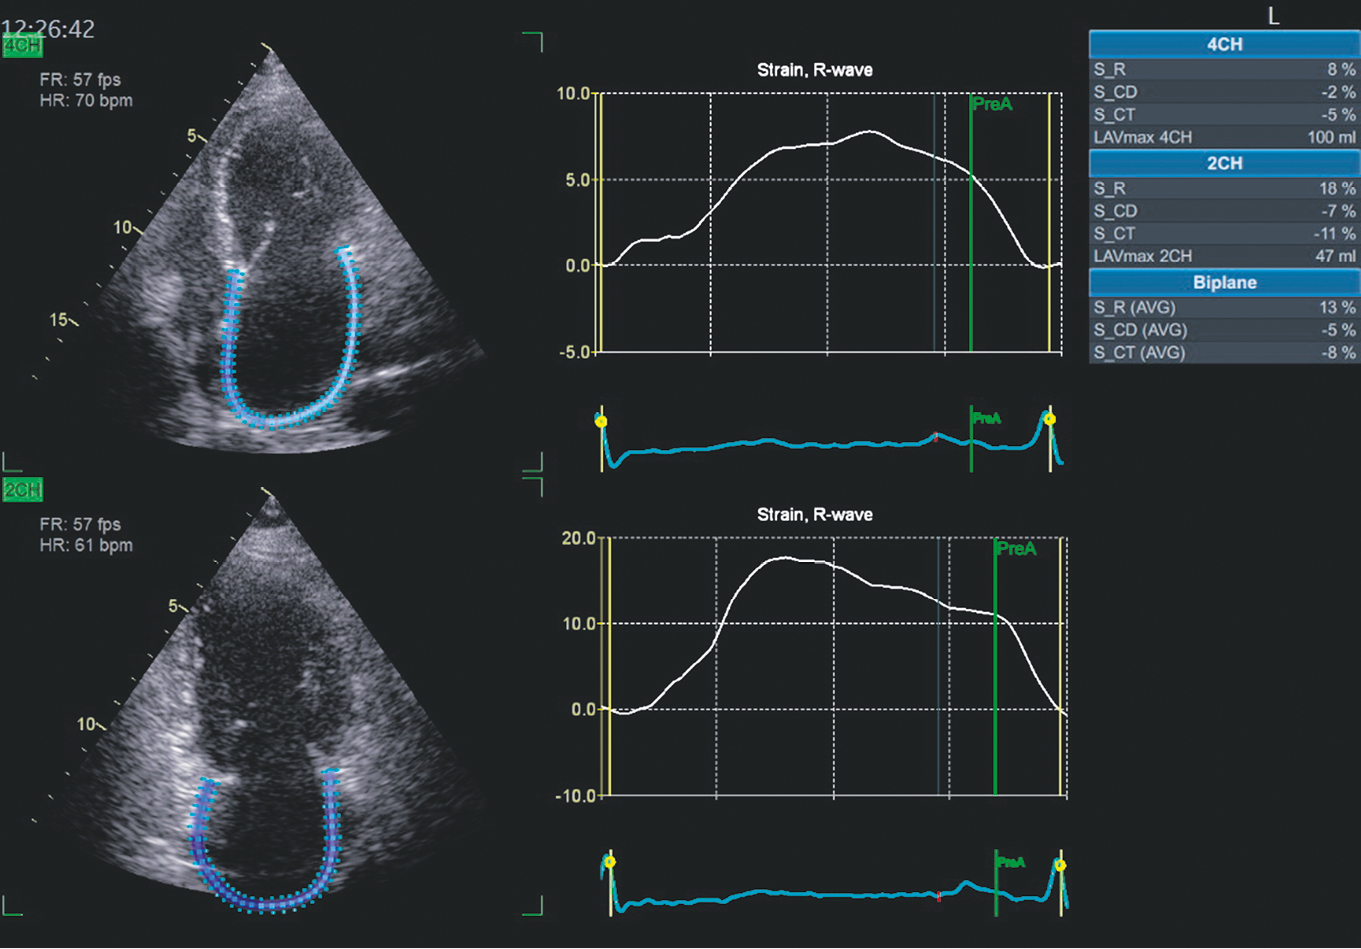

In consideration of the notable LA dilatation, LA function was evaluated in the longitudinal strain mode (2D strain) (Fig. 3). As in the case of longitudinal LV myocardial strain, LA myocardial strain parameters were abnormal. The deformation index during the reservoir phase was equal to 13% (with a mean normal value of 39%, 95% confidence interval [CI] 38%–41%). During the conduit phase, it was 5% (with a mean normal value of 23%, 95% CI 21%–25%), whereas during the contractile phase, it was 8% (with a mean normal value of 17%, 95% CI 16%–19%) [6]. Notably, the strain indices during the conduit and contractile phases were negative, as the LA myocardium shortens during these phases. For the convenient comparison of indices, it is customary to discard the minus sign. In our patient, the LA function during all three phases was significantly impaired. Because the assessment of LA myocardial strain was performed for the first time, it was not possible to ascertain the extent to which LA function had been disturbed previously.

Fig. 3. Assessment of left atrial function in 2022 in 2D-Strain mode. Explanation in the text

In addition to LV diastolic function improvement, the LA volume tended to decrease (Fig. 4). Indices of LA function have improved. Consequently, the proportion of LA myocardial strain increased from 13% to 17% during the reservoir phase, from 5% to 8% during the conduit phase, and from 8% to 9% during the contractile phase. The dynamics of the indices are presented in Table 3.

Fig. 4. Assessment of left atrial function over time in February 2024 in 2D-Strain mode. Explanation in the text